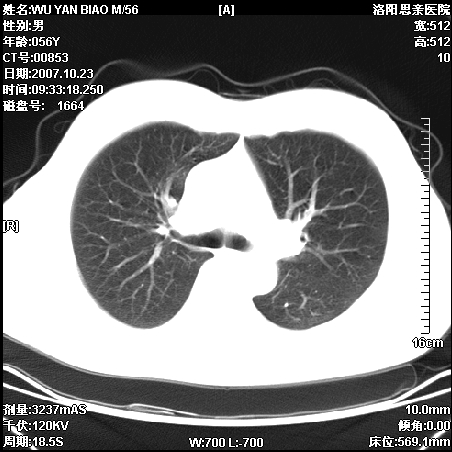

标题: CT10160:M56Y,体检发现,病人无不适,病人随访中 [打印本页]

标题: CT10160:M56Y,体检发现,病人无不适,病人随访中

后上纵隔占位,与肺交界清,宽基底附着脊柱,密度均匀,局部骨质无明确改变.

考虑;神经源性肿瘤,---起源交感n链?,不除外肠源性囊肿.

1、病灶在后纵隔脊柱旁沟内,此处是神经原性肿瘤的好发部位

2、病灶边缘光滑整齐,更说明病灶来于纵隔,由于有胸膜的包裹所以才导致这么光滑的边缘

3、病灶内的密度均匀